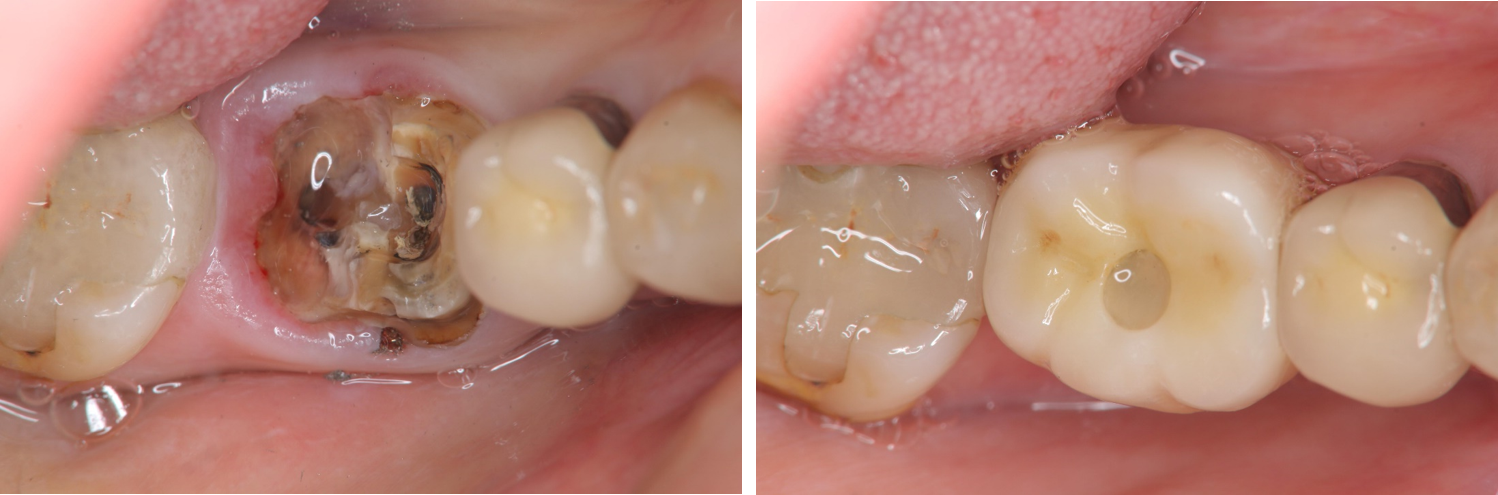

治療前,左下第一大臼齒嚴重蛀牙

治療前,蛀牙至牙根處

術前、術後比較